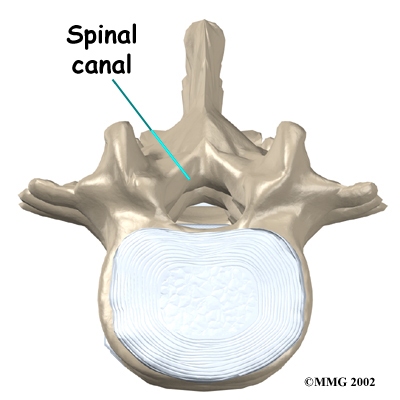

The back portion of the spinal column forms a . When the vertebrae are stacked on top of each other, these bony rings create a hollow tube. This bony tube, called the spinal canal, surrounds the as it passes through the spine. Just as the skull protects the brain, the bones of the spinal column protect the spinal cord.

In the lumbar spine, the spinal canal usually has more than enough room for the spinal nerves. The canal is normally 17 to 18 millimeters around, slightly smaller than a penny. Spinal stenosis develops when the canal shrinks to 12 millimeters or less. When the size drops below 10 millimeters, severe symptoms of lumbar spinal stenosis occur.